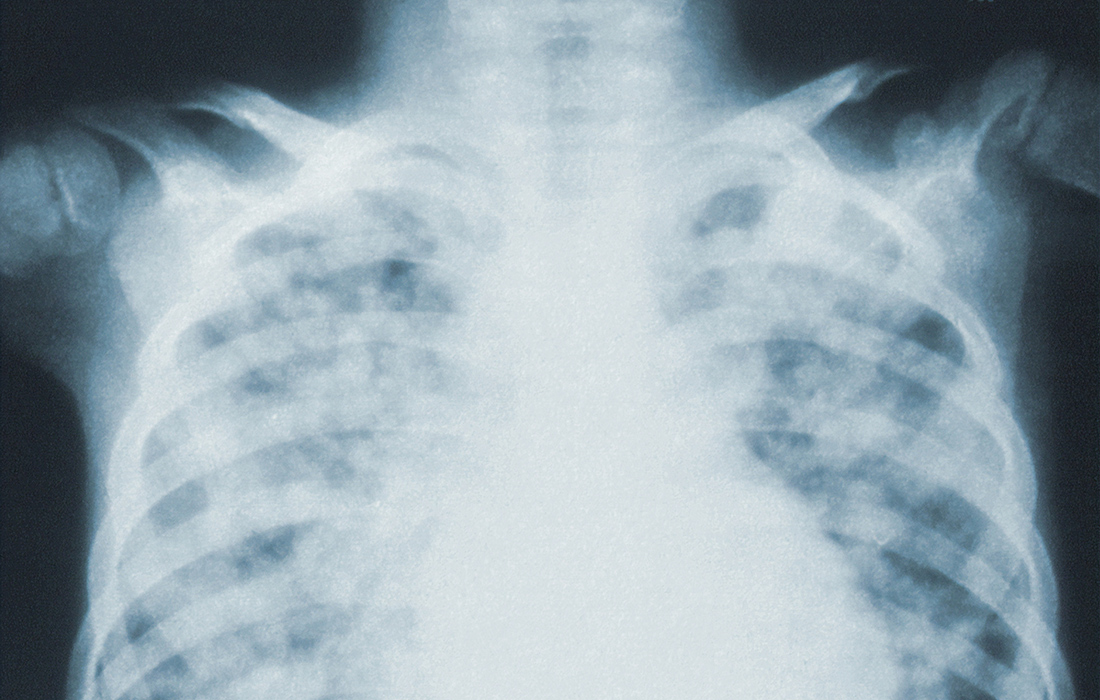

Jota contou a história de seu pai, motivo de sua preocupação. Na primeira vez que ele teve COVID, no ano passado, teve os pulmões muito comprometidos, ficou internado por um longo período e quase foi a óbito. “Eu fiquei 30 dias com ele dentro do hospital. Foi muita luta. Depois que complica é muito difícil”, lamentou.

“A cada semana o quadro pulmonar dele ia piorando, depois evoluiu para um quadro de embolia pulmonar. Chegou a ter mais de 90% do pulmão comprometido. Foi um pesadelo”, explicou. “Ele não conseguia ficar de pé sozinho, não conseguia tomar banho, não conseguia fazer suas necessidades fisiológicas, porque não tinha força”, complementou. “Nosso mundo parou por um mês”.